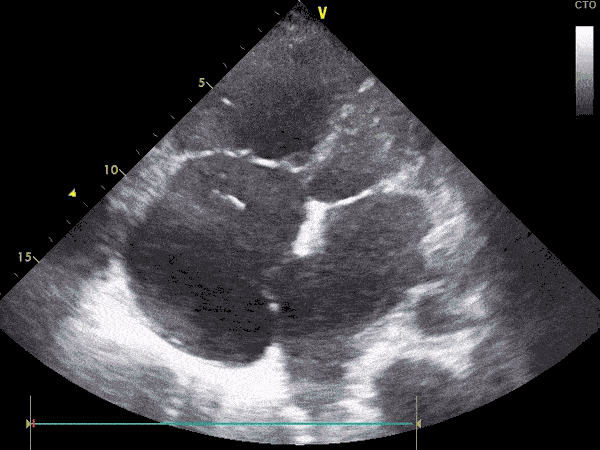

• Pamjet e mëposhtme tregojnë të njëjtën zemër të kapur me TEE dhe TTE: